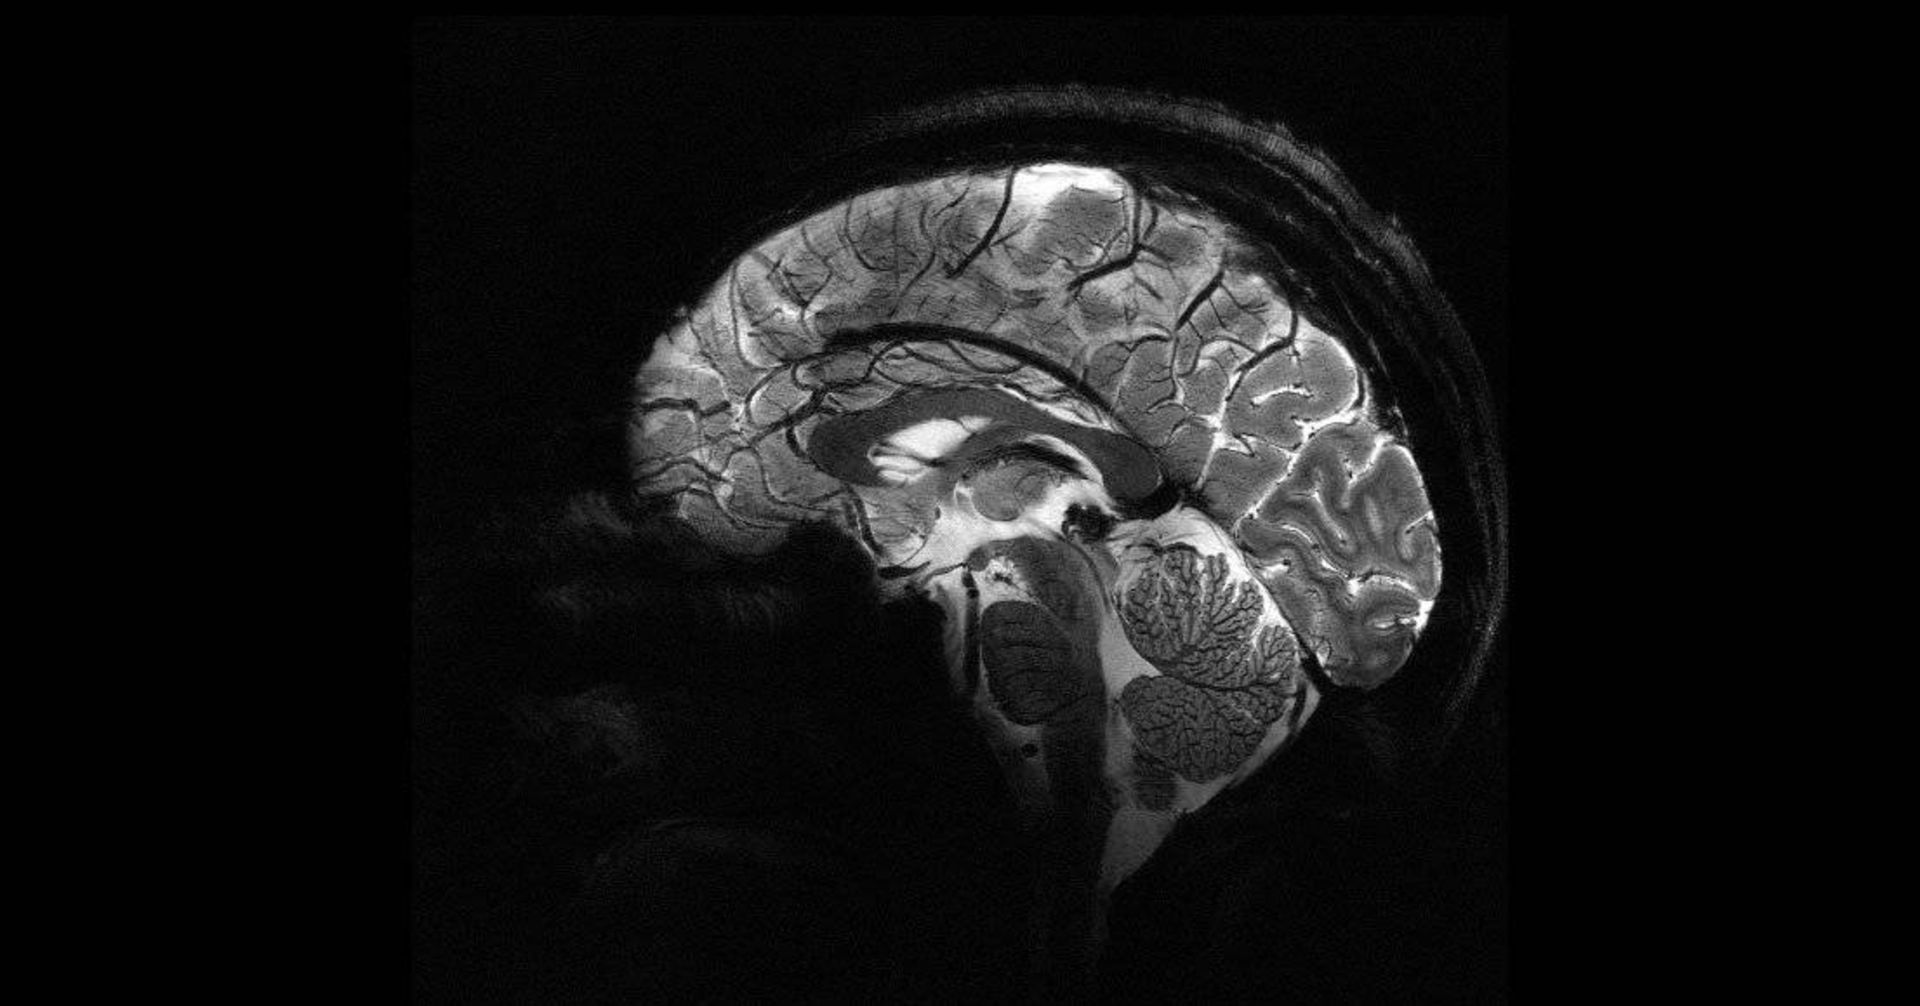

ثبت اولین تصاویر مغز انسان با قدرتمندترین دستگاه MRI جهان

قدرتمندترین اسکنر امآرآی جهان اولین تصاویر خود را از مغز انسان ارائه کرده است. تصاویر حاصل از این دستگاه از دقت بسیار بالایی برخوردار است و پژوهشگران امیدوارند بینشهای جدیدی درباره ذهن ما و بیماریهایی که آن را دچار میکند، فراهم کند.

میدان مغناطیسی ایجادشده توسط اسکنر برابر ۱۱٫۷ تسلا است که واحد اندازهگیری به نام مخترع آن نیکولا تسلا است. قدرت بالا به دستگاه جدید این امکان را میدهد که تصاویر را با دقت ۱۰ برابر بیشتر از دستگاههای امآرآی کنونی که در بیمارستانها استفاده میشود، اسکن کند. قدرت دستگاههای امآرآی مرسوم معمولا بیشتر از سه تسلا نمیشود.

ونگارد روی صفحه نمایش کامپیوتر، تصاویر گرفتهشده توسط اسکنر قدرتمند را که Iseult نام دارد، با تصاویر گرفتهشده توسط امآرآی معمولی مقایسه کرد. او گفت: «با این دستگاه میتوان عروق ریزی را که به قشر مغز خون میرسانند یا جزئیات مخچه را مشاهده کرد که تاکنون تقریبا نامرئی بود.»

یکی از اهداف اصلی ساخت چنین اسکنر قدرتمندی این است که درک دانشمندان از آناتومی مغز و همچنین این موضوع که هنگام انجام وظایف خاص، چه مناطقی از مغز فعال میشوند، بهبود پیدا کند.

دانشمندان قبلاً از MRI استفاده کرده بودند تا نشان دهند وقتی مغز چیزهای خاصی (مانند چهرهها، مکانها یا واژهها) را تشخیص میدهد، نواحی متمایزی از قشر مغز فعال میشوند. نیکلاس بولانت، مدیر علمی پروژه گفت: «استفاده از قدرت ۱۱٫۷ تسلا کمک میکند تا ارتباط بین ساختار مغز و عملکردهای شناختی را بهتر درک کنیم.»